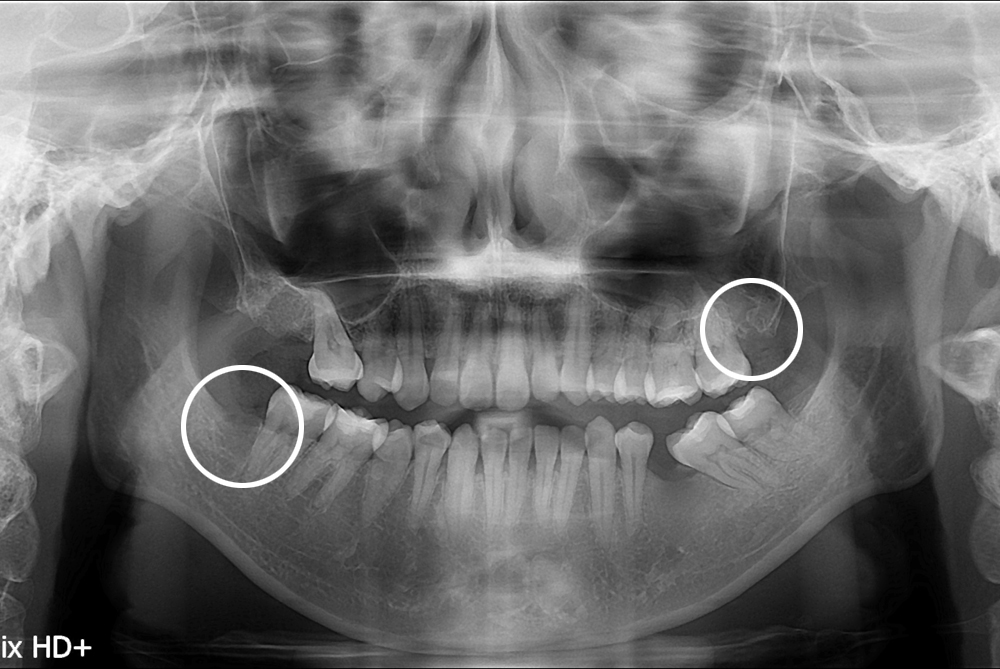

치료후 : 2017-09-21

세종치과는 구강악안면외과학 박사이신 원장님이 발치하는 치과입니다.